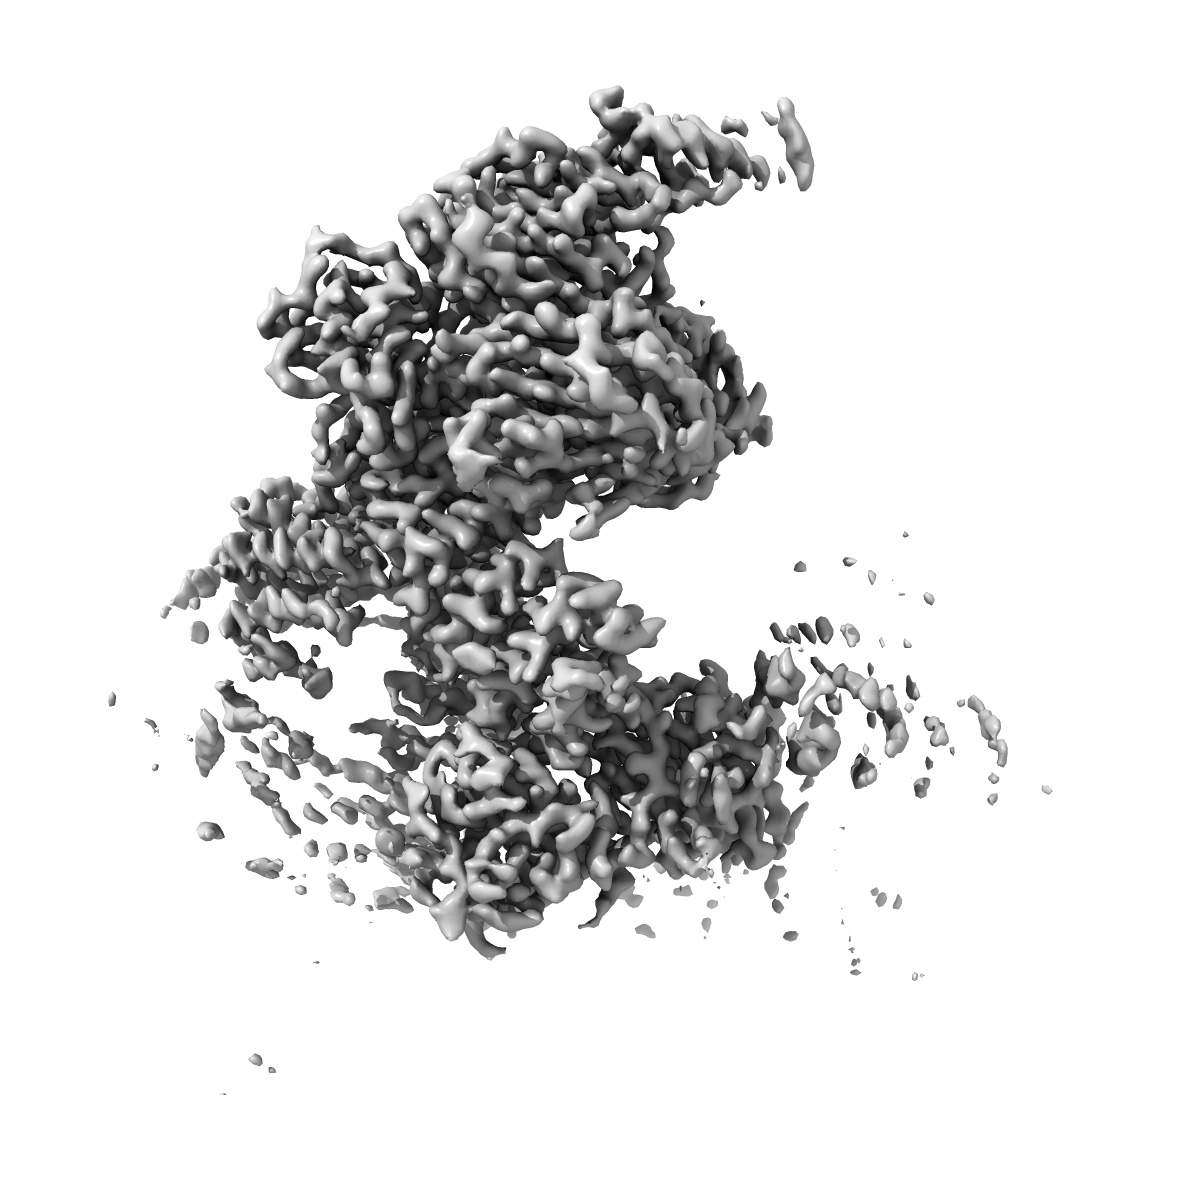

Constituent EM map: Focused refinement NTD+SPRY+Calstabin-2 of the Structure of PKA phosphorylated human RyR2-R420W in the closed state in the presence of ARM210

2.91 Å

Sample: Complex of RyR2-R420W and Calstabin-2

Structural basis for ryanodine receptor type 2 leak in heart failure and arrhythmogenic disorders.

Miotto MC , Reiken S, Wronska A , Yuan Q, Dridi H , Liu Y, Weninger G , Tchagou C, Marks AR

(2024) Nat Commun , 15 , 8080 - 8080